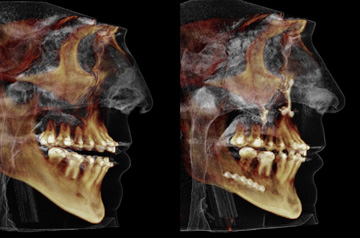

Face and Bite Correction

Primary Diagnoses

- Open bite

- Relapse after orthodontic treatment

Surgical solution

- Upper Jaw Osteotomy

- Lower Jaw Osteotomy

- Airway and Bite Correction

Surgery was performed in 2016 at our Face Smile Center by Dr. Andrey Senyuk, oral and maxillofacial surgeon.